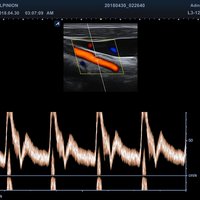

• PW-Doppler (Pulsed-Wave): Verfahren, das ein Geschwindigkeitsspektrum von beweglichem Gewebe und Flüssigkeiten an einer bestimmten Position liefert

• Farbdoppler: farbige Darstellung der Richtung des Blutflusses

• Powerdoppler: sensitive, farbige Darstellung des Blutflusses unabhängig von Geschwindigkeit und Richtung